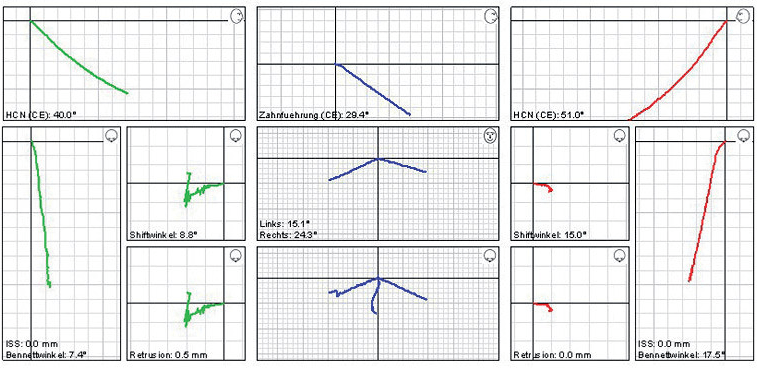

Szükség lehet speciális gyógytornára, egyénre szabott éjszakai sín hordására, akár megfelelő fogszabályozó készülék, illetve fogpótlás elkészítésére is. Ilyen esetekben speciális bemérésre van szükség, amihez úgynevezett nyílhegyrajzoló készüléket, arcívet, pozíciós harapásokat használunk, és segítségül hívhatjuk a legmodernebb, erre a célra létrehozott készüléket: az ARCUSdigmát.

Az állkapocs helyzetének, mozgásának megállapítására, esetleges hibáinak felderítésére az ARCUSdigma rendszer szolgál. A KaVo ARCUSdigma egy elektronikus regisztrációs rendszer, amely 3 dimenziós, ultrahangos méréseken alapul, a páciens egyéni alsóállkapocs-mozgásait méri a koponyához viszonyítva, minden olyan beállítási értéket kiszámít a fogtechnikusok számára, amelyek az artikulátor programozásához és az egyedi, funkcionális fogpótlások készítéséhez szükségesek.

Majd ezt követően arcívvel meghatároztam a felső állcsont koponyához való elhelyezkedését, intraorális rajzolóeszközzel a felső és az alsó állcsont egymáshoz való viszonyát, majd az Arcus Digma készülékkel az individuális mozgáspályákat. Ez mind szükséges ahhoz, hogy egyedi, az egyén számára legkényelmesebb fogpótlás elkészülhessen, melytől jelen esetben páciensünk panaszainak rendeződését vártam.